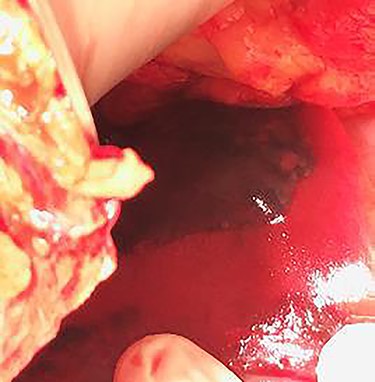

An emergency c-section was performed, during which a massive hemoperitoneum was observed. It was subsequently converted to median laparotomy and a subcapsular hepatic hematoma involving the entire left lobe was found, with rupture and active hemorrhage. Hepatic packing was performed. However, the patient continued to bleed profusely. Therefore, a Vicryl® prosthesis involving the left lobe was placed to effectively control the hemorrhage (Fig. 1).

As far as the surgical approach is concerned, an immediate hepatic packing was performed in both patients. However, it was not possible to fully control the hemorrhage in the first patient, so a Vicryl® prosthesis was placed, commonly used in post-traumatic splenic lacerations. It was adapted ‘in situ’ to this particular situation to cover the entire left lobe of the liver. This is an uncommon approach according to the literature. It is mainly described in the context of trauma surgery as a life-saving measure.